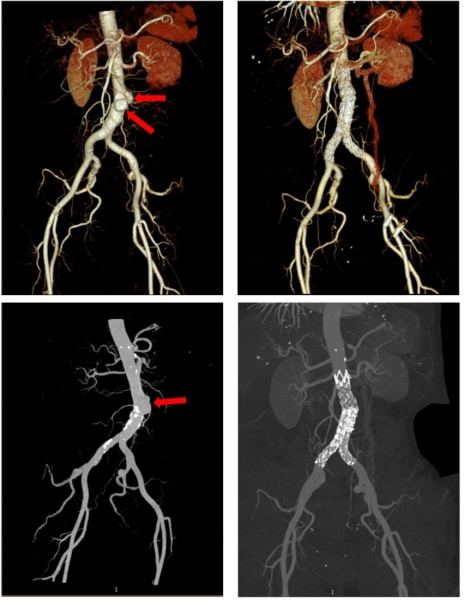

CT检查(计算机断层扫描)

CT利用X射线束对人体进行多层扫描,通过计算机重建出三维图像,提供更详细的解剖信息。

1.高分辨率三维图像:可以清晰地显示器官、血管、骨骼的细节。

2.多功能性:适用于全身各部位的检查,尤其是复杂病变。

●血管病变:如动脉瘤、血管狭窄等。

●精准诊断:CT能够提供更详细的影像信息,帮助医生明确病变的性质、范围和严重程度。

●治疗指导:在手术前或放疗前,CT可以为医生提供精确的解剖信息,辅助制定治疗方案。

●疾病监测:用于肿瘤、血管病变等疾病的随访和疗效评估。